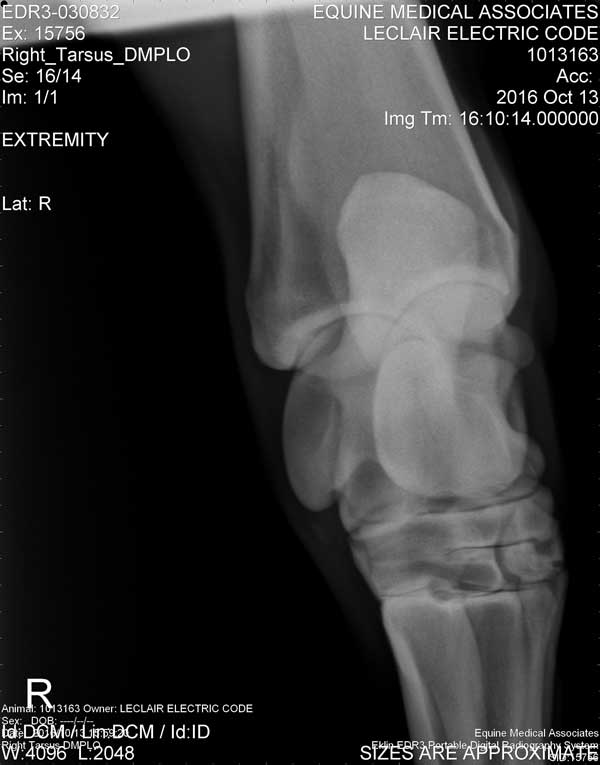

Electric Code is 11 years old at the time these X-Rays were taken on October 13, 2016

Hock/Tarsal

Right